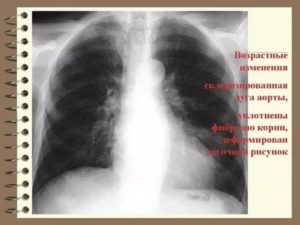

Важно! Рентгенограмма позволяет определять не только заболевания лёгких, но и костей. В частности, можно обнаружить сколиоз, травмы рёбер, а в некоторых случаях и поражения диафрагмы.

В первую очередь врачи обращают внимание на корни лёгких — структуры, которые являются так называемыми воротами в лёгкие.

В норме на рентгенограмме они не увеличены, на их фоне не видны никакие образования. Само расположение корней также имеет значение.

Корни делят на три сектора — верхний, средний и нижний. Правый корень напоминает искривлённую ленту, которая средне выражена и сужается книзу.

Верхняя часть этого корня расположена на том же уровне, что и передний отрезок второго ребра — второго межрёберья. Верхняя часть левого корня расположена на одно ребро выше правого, а сам он частично скрыт тенью от сердца.

Ширина артериального ствола корней, в большинстве случаев, не превышает 15 миллиметров.

Сами корни подразделяются на магистральные и рассыпчатые. Первый вид предполагает большую верхнюю часть (головку), которая в основном представлена лёгочной артерией. Рассыпчатые же корни обладают большой разветвлённой сетью сосудов, которые переходят в тяжи.

Помимо ранее упомянутых новообразований, можно отметить следующие характеристики корней, которые обозначаются в письменных заключениях, являются отклонениями от нормы и могут быть признаками патологий: уплотненные, тяжистые и расширенные корни, также корни могут быть усилены.

Обычно это происходит из-за отёка бронхов или крупных сосудов. А в некоторых случаях и из-за того, что происходит увеличение лимфоузлов.

Уплотнение и расширение ткани корней почти всегда происходит одновременно, если же корни только уплотнены, это говорит о хроническом процессе.

На снимке расширенные корни будут выглядеть менее чёткими, а также крупнее стандартных размеров.

Корни расширены, уплотнены

Корни легких — это главный бронх, бронхиальные артерии, легочная артерия и легочная вена. Это один из распространенных диагнозов, свидетельствует о каких-то хронических процессах, происходящих в легких. Хронический бронхит, отеки, пневмонии, воспаления легких.

Если у вас в заключении написано «корни уплотнены, расширены», то это говорит о том, что у вас идет хронический воспалительный процесс в легких. У курильщиков со стажем нередко встречается именно такой результат флюорографии.